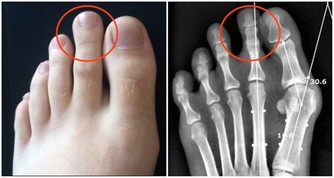

第五、有助腎臟排泄

紅酒有助於腎臟排泄尿酸和預防痛風、風濕病和關節炎。